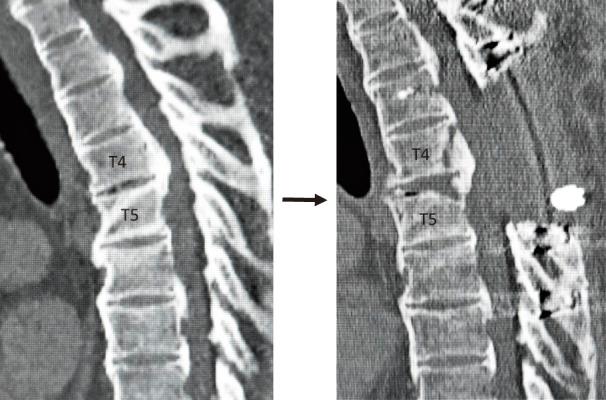

根据后纵韧带骨化(OPLL)的部位及形态,针对OPLL所致胸段脊髓病的减压手术,已开展了多种经前路或后路的手术方法,有无脊髓固定均可。其中,胸段中节段(T4/T5 - T7/T8)的前路减压尤为困难,因其解剖结构特殊,该部位脊柱呈后凸畸形,且附近有包含循环呼吸器官的胸廓。在此节段的前路减压手术中,后路手术相比前路具有多种优势。在前路手术中,操作复杂,脊髓减压效果只能通过直接切除OPLL或使其前路漂浮来实现。然而,此时最易发生脊髓损伤和硬脊膜撕裂等并发症。相反,后路手术操作简单,可选择多种减压方式,包括椎板切除术、椎板成形术、矫正后凸手术、分期减压手术(铃木法)、单纯后路环形减压(大冢法)以及前后联合入路环形减压(富田法)。其中,在椎板切除术、椎板成形术和矫正后凸手术中,无需对OPLL进行直接操作即可在一定程度上实现前路减压。在大冢法中,尽管技术要求较高,但单纯后路即可实现完全减压。为避免并发症,尤其是硬脊膜与OPLL严重粘连的患者,最好将削薄并分离的OPLL向前移位,而非试图完全切除。